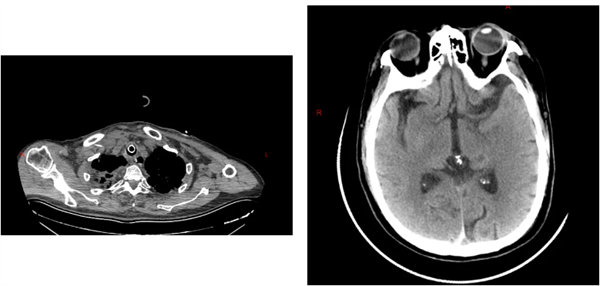

7月,賈先生因車禍導致全身多發傷急診入院,診斷結果觸目驚心:重癥肺炎、膿毒性休克、I型呼吸衰竭、右側脛腓骨下端開放性粉碎性骨折、骨盆多發骨折、左側多發肋骨骨折、創傷性硬膜下出血等13項嚴重損傷,高齡、重癥、多發傷的疊加讓救治難度陡增。重癥醫學科第一時間啟動緊急救治,抗感染、抗休克、呼吸機支持等一系列關鍵措施精準落地,為患者筑牢生命防線。待病情相對穩定后,患者轉入專科進一步治療,開啟了分階段的精準修復之路。